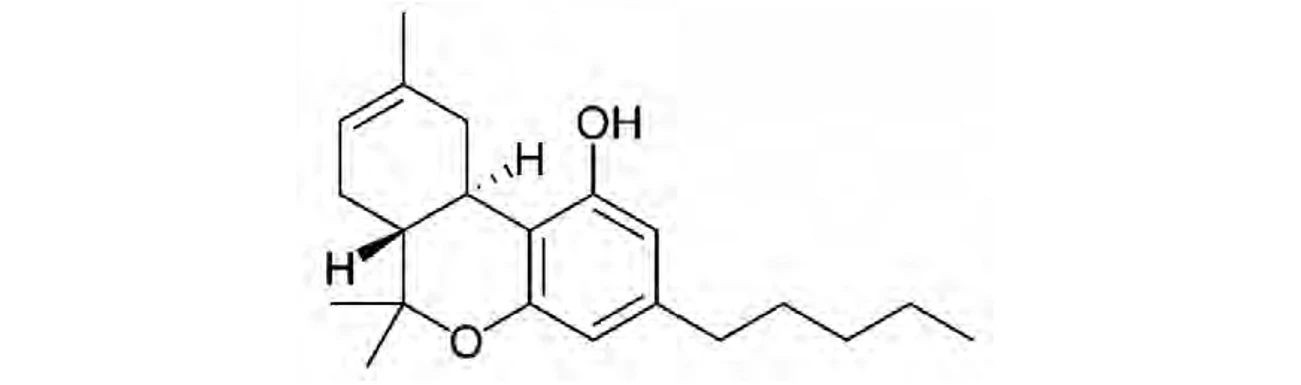

PČR: Δ9-trans-tetrahydrokanabinol (THC) – byl objeven v roce 1964 Gaonim a Mechoulamem, jedná se o psychoaktivní kanabinoid (10), rozpustnost ve vodě je 2,8 mg/l při 298,15 K (14)

PČR: Δ9-trans-tetrahydrokanabinol (THC) – byl objeven v roce 1964 Gaonim a Mechoulamem, jedná se o psychoaktivní kanabinoid (10), rozpustnost ve vodě je 2,8 mg/l při 298,15 K (14)

Biosyntéza (Obr. 5) začíná vytvořením dvou kanabinoidních prekurzorů – geranyldifosfátu a olivetové kyseliny, které spolu kondenzují za účasti geranyltransferasy a vzniku kanabigerolové kyseliny (CBGA). CBGA se následně transformuje na tetrahydrokanabinolovou kyselinu (THCA), kanabidiolovou kyselinu (CBDA) a kanabichromenovou kyselinu (CBCA) pomocí THCA synthasy, CBDA synthasy a CBCA synthasy. Tetrahydrokanabinol (THC), kanabidiol (CBD), kanabigerol (CBG) a kanabichromen (CBC) vznikají dekarboxylací ze svých kyselin během skladování vlivem tepla a světla za uvolnění CO211. THC a iso-THC mohou také vznikat kysele katalyzovanou cyklizací CBD vytvořením příslušných karbokationtů na C-8 a C-1 CBD skeletu (25).

THC se v lidském těle oxiduje cytochromem P452, subtyp 2C9 (CYP2C9) na THC-11-ovou kyselinu (THC-COOH), která nevykazuje psychotropní účinky. Jedná se o tříkrokový proces přes hydroxylovaný a aldehydový intermediát (Obr. 6). THC-COOH a její glukuronidy jsou klíčovými analyty ve vzorcích moči při použití forenzních esejí indikujících užití marihuany (16,26). CBD se metabolizuje podobně. Prvním krokem je hydroxylace na C-7 konci, dochází k vytvoření 7-hydroxy-CBD, následuje další oxidace vedoucí k vytvoření CBD-7-ové kyseliny a hydroxylovaných derivátů této kyseliny. Dále se tvoří glukuronidy těchto oxidovaných metabolitů25.